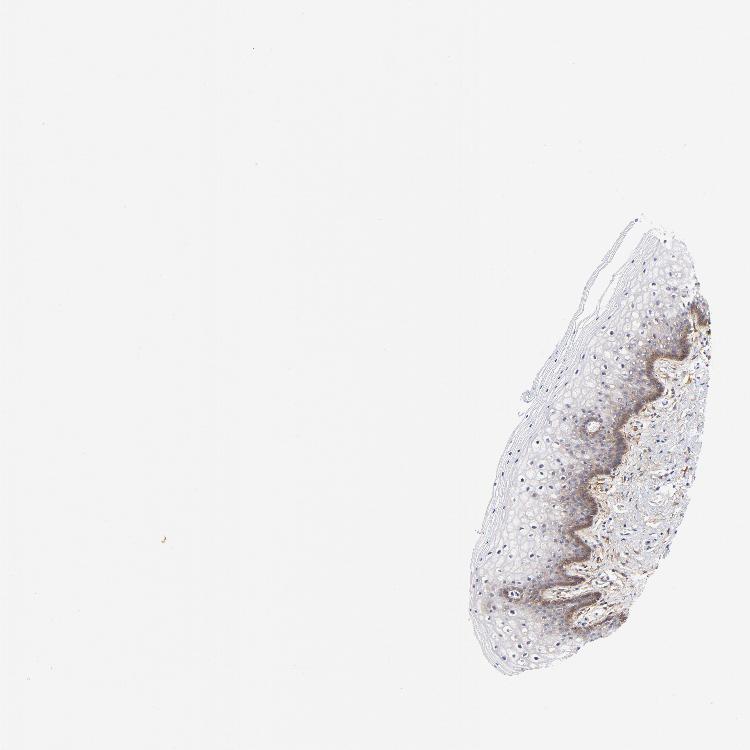

VAGINA - Antibody stainingi

Antibody staining in the annotated cell types in the current human tissue is reported as not detected, low, medium, or high, based on conventional immunohistochemistry profiling in selected tissues. This score is based on the combination of the staining intensity and fraction of stained cells.

Each image is clickable and will lead to virtual microscopy that enables deeper exploration of all samples and also displays staining intensity scores, fraction scores and subcellular localization as well as patient and tissue information for each sample.

Antibody HPA003222

Squamous epithelial cells Low